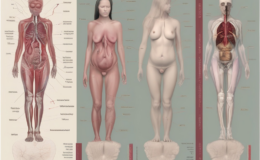

Kemik metastazı, kanser hücrelerinin vücudun başka bir bölgesinden kemiklere yayılması sonucu oluşur. Bu durum, genellikle ileri evre kanserlerin bir belirtisi olarak kabul edilir ve hastaların yaşam kalitesini ciddi şekilde etkileyebilir. Kemik metastazının anlaşılması, bu karmaşık süreci aydınlatmak ve hastalara doğru bilgilendirme sağlamak açısından çok önemlidir.

Kemikler, vücudun en dayanıklı yapılarından biri olmasına rağmen, kanser hücrelerinin hedefi haline gelebilir. Kemik metastazı, genellikle meme, akciğer, prostat ve böbrek kanserlerinin bir sonucu olarak ortaya çıkar. Bu hücreler, kan dolaşımı veya lenf sistemi yoluyla kemiklere ulaşabilir. Kemik metastazı, kanserin farklı bir yapıya uyum sağlama kapasitesini göstermesi açısından önemlidir.

Kemik metastazı, genellikle ileri evre kanserlerin bir sonucu olarak ortaya çıkar ve birçok hasta için ciddi sağlık sorunlarına yol açabilir. Bu durumun erken belirtilerini tanımak, tedavi sürecini hızlandırmak ve yaşam kalitesini artırmak için hayati önem taşır. Belirtiler kişiden kişiye değişebilse de, bazı yaygın semptomlar dikkatle izlenmelidir.

Kemik metastazının belirtileri, metastazın bulunduğu bölgeye ve yaygınlık derecesine bağlı olarak değişir. Ancak, bazı genel belirtiler şu şekilde sıralanabilir: